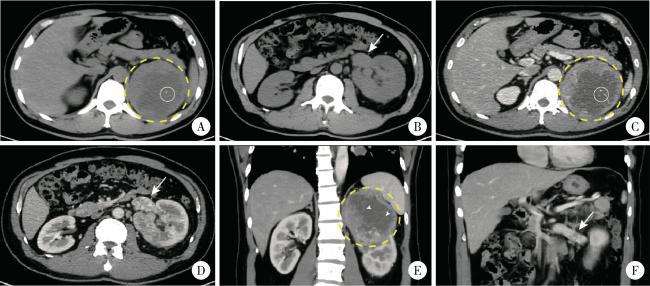

图1 1例合并Mayo 0级肾静脉癌栓的TFE3重排肾细胞癌患者(病例8)的增强CT影像Figure 1 Contrast-enhanced CT images from a left-sided TFE3 -rearranged renal cell carcinoma patient combined with Mayo level 0 renal vein thrombus (case 8) A, B, 9.4×9.6×9.5 cm mass was identified in the upper pole of the left kidney, the margin of the mass was well-defined; on non-contrast CT scan, the mass (yellow circle with dashed line) demonstrated heterogeneous soft tissue density (50-70 HU) with patchy areas of low density (30-40 HU); central punctate calcifications were observed within the lesion (white circle with solid line); the left renal vein was dilated (white arrow, axial plane). C, D, on contrast-enhanced CT imaging (arterial phase), the solid components of the mass showed marked heterogeneous enhancement (80-120 HU), while the cystic areas within the lesion exhibited no obvious enhancement; tumor thrombus was identified within the renal vein (white arrow), measuring approximately 3.7 cm in length (axial plane). E, F, on contrast-enhanced CT imaging (arterial phase), multiple fine septations were visible within the cystic areas and demonstrated enhancement (white arrow head); the perirenal fascia was compressed, and the lesion was in close proximity to the left adrenal gland and spleen; the left renal vein exhibited a filling defect and indicated tumor thrombus (white arrow); no significantly enlarged lymph nodes were seen (coronal plane). |